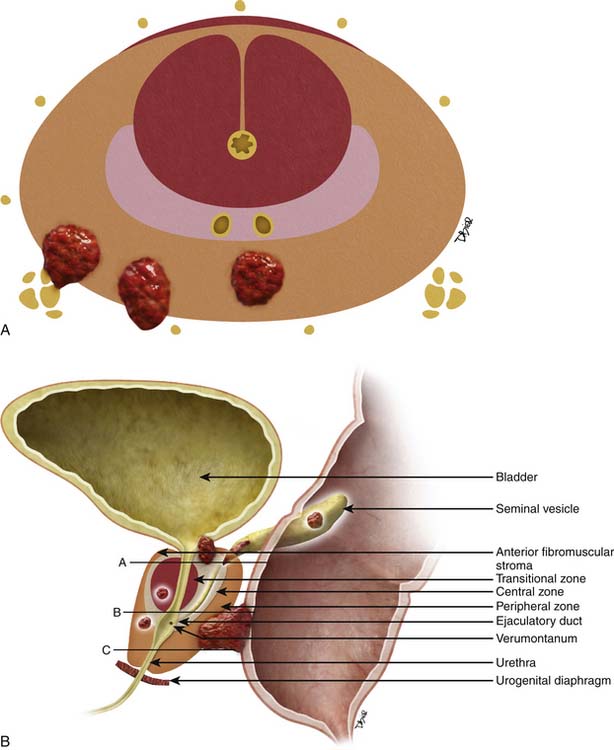

Staging and grading | Early prostate cancer – Macmillan Cancer Support